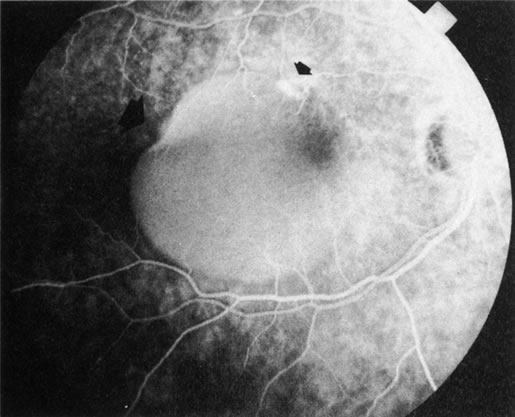

Fig. 3. Notched retinal pigment epithelium (RPE) detachment. There is a notch at the superotemporal border of a large RPE detachment that fills unevenly with fluorescein (large arrowhead). There is also a superior neovascular complex (small arrowhead) that hyperfluoresces. (Courtesy of Dr. Kenneth G. Noble.)